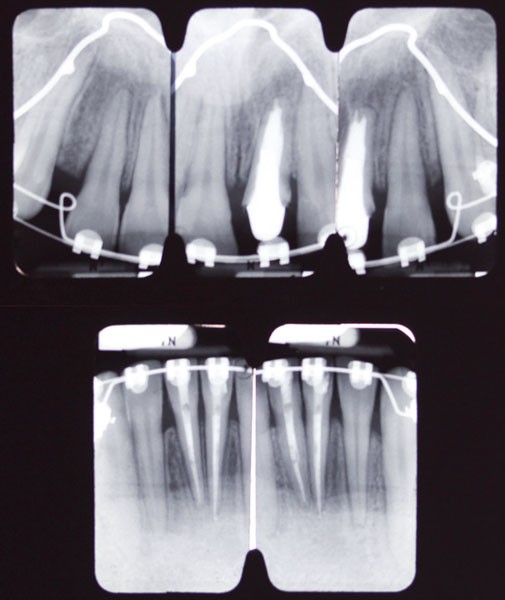

Il est donc légitime de se poser la question de l’innocuité des traitements orthodontiques sur la santé pulpaire.

Nous allons tenter d’élucider ce problème, en analysant successivement les effets directs et indirects, que l’orthodontie est supposée avoir sur le complexe dentino-pulpaire.